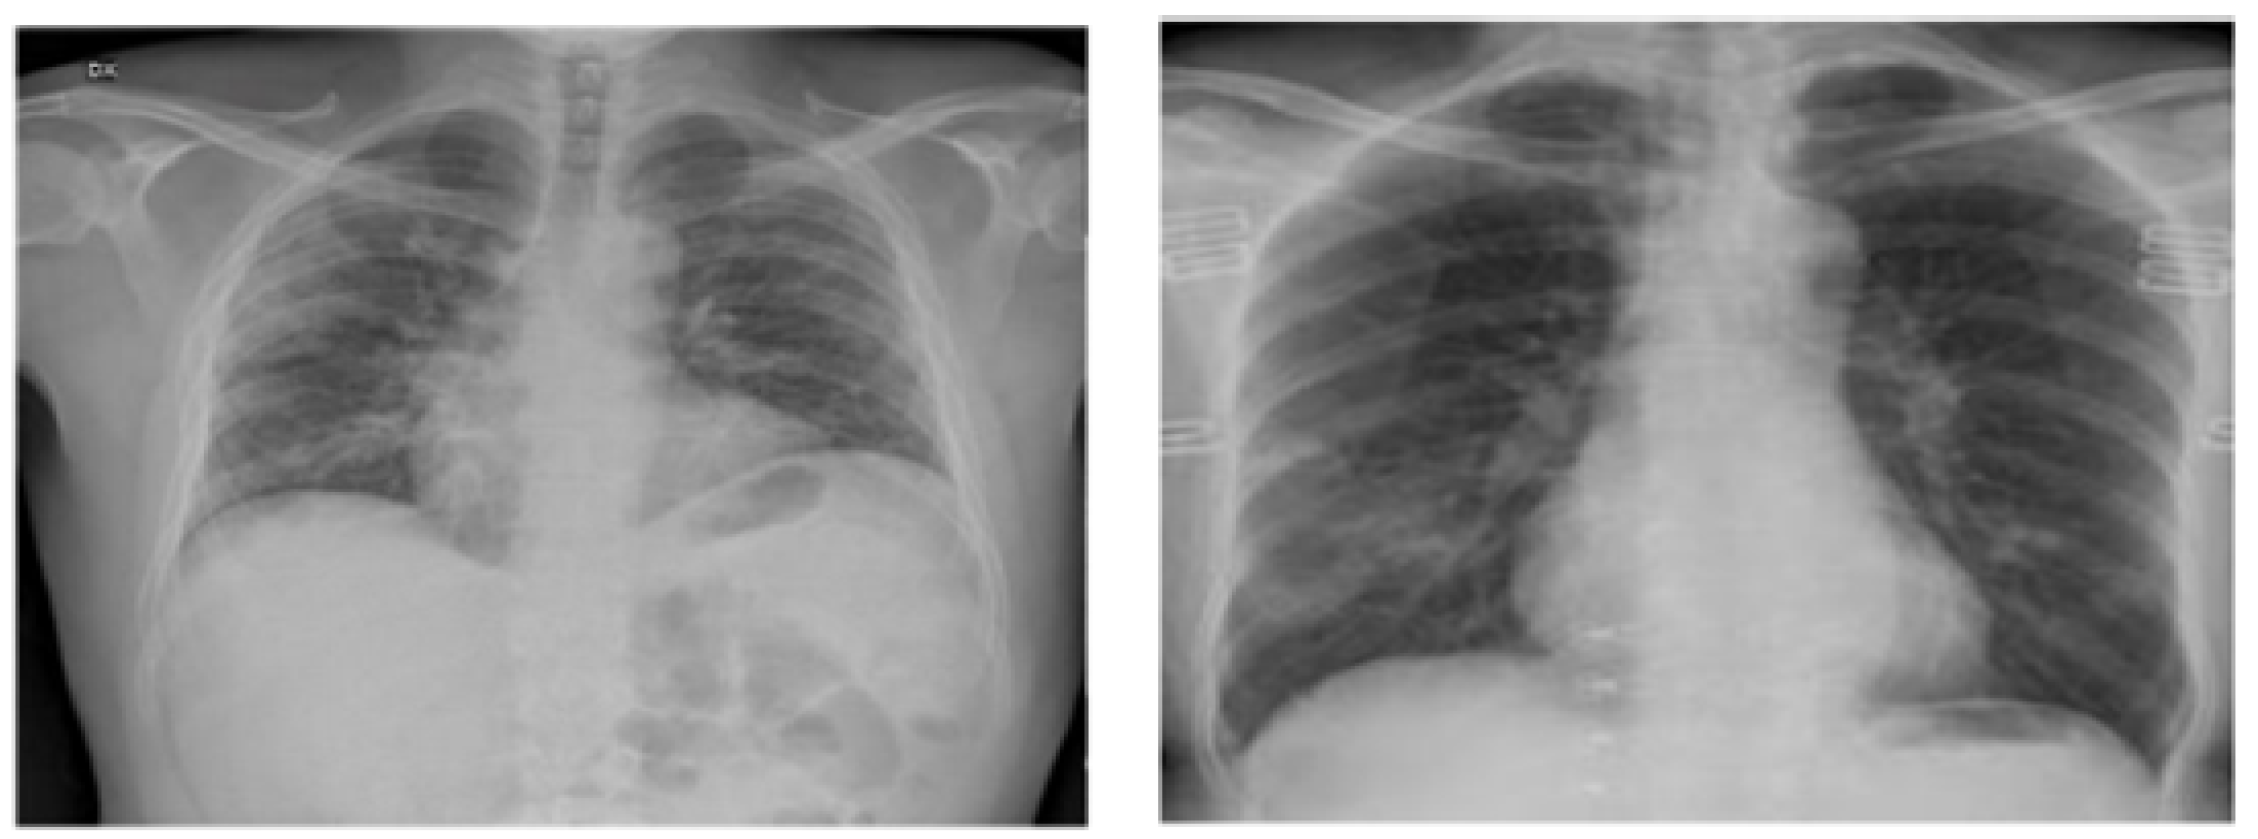

The evaluation framework known as the ImageNet Large Scale Visual Recognition Challenge (ILSVRC) serves as a robust assessment tool for large-scale object detection and image categorization methods (Figure 3). One overarching goal of this framework is to facilitate a broader comparison of progress in object detection across a diverse spectrum of objects, effectively leveraging the considerable effort invested in labeling tasks. The extensive ImageNet dataset comprises a staggering 14,197,122 images, meticulously labeled according to the WordNet hierarchy. Since its inception in 2010, this dataset has served as the cornerstone of the ImageNet Large Scale Visual Recognition Challenge (ILSVRC), an esteemed benchmark for image classification and object recognition. The publicly accessible dataset features images that have undergone meticulous manual annotation. Moreover, a subset of test images intentionally excludes these manual annotations, enhancing the rigor of the benchmark. ILSVRC annotations assume two primary forms: Firstly, image-level annotations capture binary labels indicating the presence or absence of an object class within an image. For instance, these annotations might convey the message “this image contains cars” while simultaneously noting “there are no tigers present”. Secondly, object-level annotations offer comprehensive bounding boxes and class labels for individual object instances in images. These meticulous annotations enhance the benchmark’s ability to address both image and object-level recognition challenges.

Figure 3.

Samples of normal X-ray images [4].

The collection of chest X-rays from patients with COVID-19 was sourced from an open-access data repository. This database encompasses a comprehensive set of chest X-ray images, comprising 1184 images of individuals confirmed as COVID-positive and 1319 images of individuals without COVID-19 diagnosis. Our investigation is fundamentally grounded in this database, which organizes chest radiography images into two distinct categories, as visually represented in Figure 4. The categories include individuals who exhibit no infection and individuals who have been diagnosed with COVID-19. To facilitate our research and maintain robust evaluation practices, we randomly partitioned this dataset into two distinct subsets. The division allocated 80% of the images for the training phase, enabling model development and refinement, while the remaining 20% were reserved for testing, serving as an independent validation dataset. This partitioning strategy ensures a reliable assessment of our models and their generalization capabilities.

Figure 4.

Sample of infected X-ray images [4].